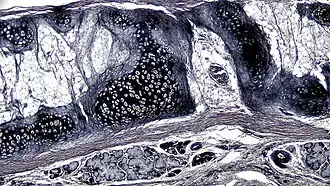

![]() A cross section of mammalian elastic cartilage | |

Elastic cartilage, fibroelastic cartilage or yellow fibrocartilage [1] is a type of cartilage present in the pinnae (auricles) of the ear giving it shape,[2] provides shape for the lateral region of the external auditory meatus,[3] medial part of the auditory canal[3] Eustachian tube, corniculate and cuneiform laryneal cartilages,[3] and the epiglottis. It contains elastic fiber networks and collagen type II fibers.[4] The principal protein is elastin.

Elastic cartilage is histologically similar to hyaline cartilage but contains many yellow elastic fibers lying in a solid matrix. These fibers form bundles that appear dark under a microscope. The elastic fibers require special staining since when it is stained using haematoxylin and eosin (H&E) stain it appears the same as hyaline cartilage.[3] Verhoeff van Geison stains are used (giving the elastic fibers a black color), but aldehyde fuchsin stains, Weigert's elastic stains, and orcein stains also work.[3] These fibers give elastic cartilage great flexibility so that it is able to withstand repeated bending. Similarly to hyaline one or multiple chondrocytes lie between the spaces (or lacunea) in the fibres.[2] The chondrocytes only make up 2% of the tissue's volume.[2] Chondrocytes and the extracellular matrix are contained in an outerlayer named the perichondrium[2] (which is a layer of dense irregular connective tissue that surrounds cartilage which is independent of the joint).[3] It is found in the epiglottis (part of the larynx), and the pinnae (the external ear flaps of many mammals). Elastin fibers stain dark purple/black with Verhoeff's stain.

The extracellular matrix contains elastin, fibrillin, glycoproteins, collagen types II, IX, X, and XI, and the proteoglycan aggrecan.[2] the components within the extracellular matrix are produced by the chondroblasts located within the edges of the perichondrium.[2]